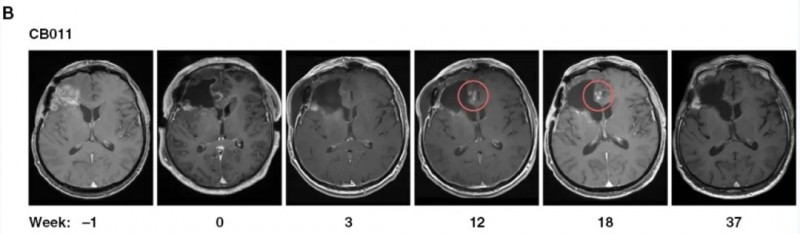

此外,56%的患者在复发手术联合7~37周CAR-NK治疗后达到病情稳定(SD)。值得注意的是,2例患者在注射部位出现假性进展,提示存在治疗诱导的免疫反应。MRI检查显示,CAR-NK注射后第12周,患者切除边缘附近出现斑点状对比增强,且该现象在后续几周内自行消失,推测与诱导的免疫反应相关,无需额外治疗(详见下图)。

▲图源“Neuro-Oncology”,版权归原作者所有,如无意中侵犯了知识产权,请联系我们删除